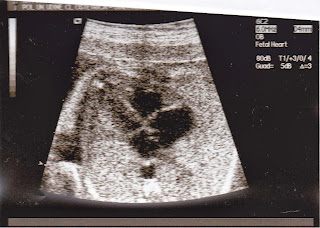

![]() |

| Gorgeous heart<3 |